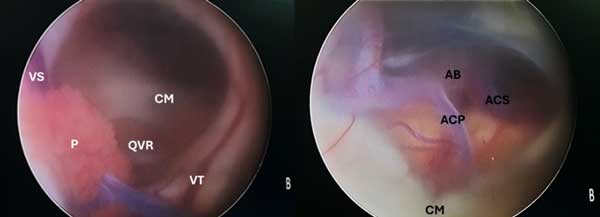

Se decidió realizar una derivación ventriculoperitoneal (VDVP) para remisión total de los síntomas. La paciente estuvo aproximadamente un año libre de enfermedad con control por imágenes satisfactorio (Figura 3). Posteriormente, consultó por reaparición de síntomas. La semiología valvular arrojó pulsor rígido y la TC cerebral de control mostró dilatación ventricular por lo que se efectuó cirugía de revisión en la que se halló disfunción valvular distal secundaria a obstrucción por detritus celulares. Se repermeabilizó el catéter distal y se volvió a colocar en cavidad peritoneal resolviendo la signo-sintomatología que manifestaba. Desafortunadamente presentó una escara cutánea en la herida cefálica con exposición del reservorio valvular que requirió cirugía de toilette y extracción completa del dispositivo más tratamiento antibiótico. Evolucionó con incremento progresivo de los trastornos de la marcha por lo que se programó una tercera ventriculostomía endoscópica (TVE), en la que se observó la impronta del espacio de Virchow-Robin en el tálamo posterior, el piso del tercer ventrículo abierto y la membrana de Liliequist ya fenestrada (Figura 4). Finalmente, se determinó colocar una válvula de derivación ventriculoperitoneal (VDVP) contralateral con evolución favorable.

Figura 4. Imagen intraoperatoria endoscópica de abordaje al ventrículo lateral derecho donde se observa, a la izquierda, la impronta generada por la dilatación del espacio de Virchow-Robin y en la imagen derecha el piso del tercer ventrículo abierto y la membrana de Liliequist ya fenestrada. P: Plexo coroideo. VS: Vena septal. VT: Vena tálamo estriada. QVR: Impronta de quiste de Virchow-Robin. CM: Cuerpos mamilares. AB: Arteria basilar. ACP: Arteria cerebral posterior. ACS: Arteria cerebelosa superior.